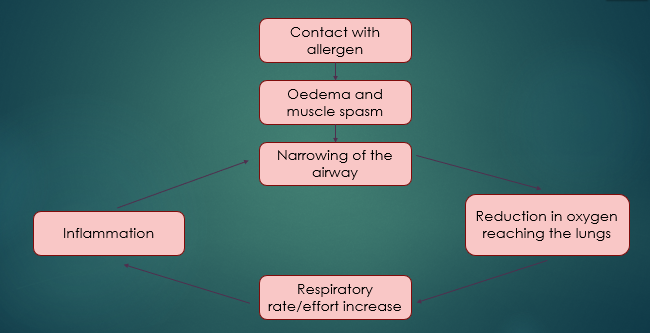

Anaphylaxis

Contact with allergen

Oedema and muscle spasm

Narrowing of the airway

Inflammation OR Reduction in oxygen reaching the lungs

Respiratory rate/effort increases

What is anaphylaxis?

A severe allergic reaction, body reacts, so becomes hypersensitive to a foreign substance

Patient has contact with the allergen - this is usually inhalation but can be caused by something else, such as a wasp/bee sting or blood transfusion reaction

It is in serve cases that we get respiratory distress

After the patient has come into contact with the allergen, Oedema occurs ..

Swelling and muscle spasm

This then causes a narrowing of the airway, so less o2 gets into the body

That’s what compensatory mechanisms kick in = increase respiration effort and rate, but this causes more inflammation and more narrowing

Becomes a vicious cycle of the body trying to correct it but the compensatory mechanisms are increasing the inflammatory response